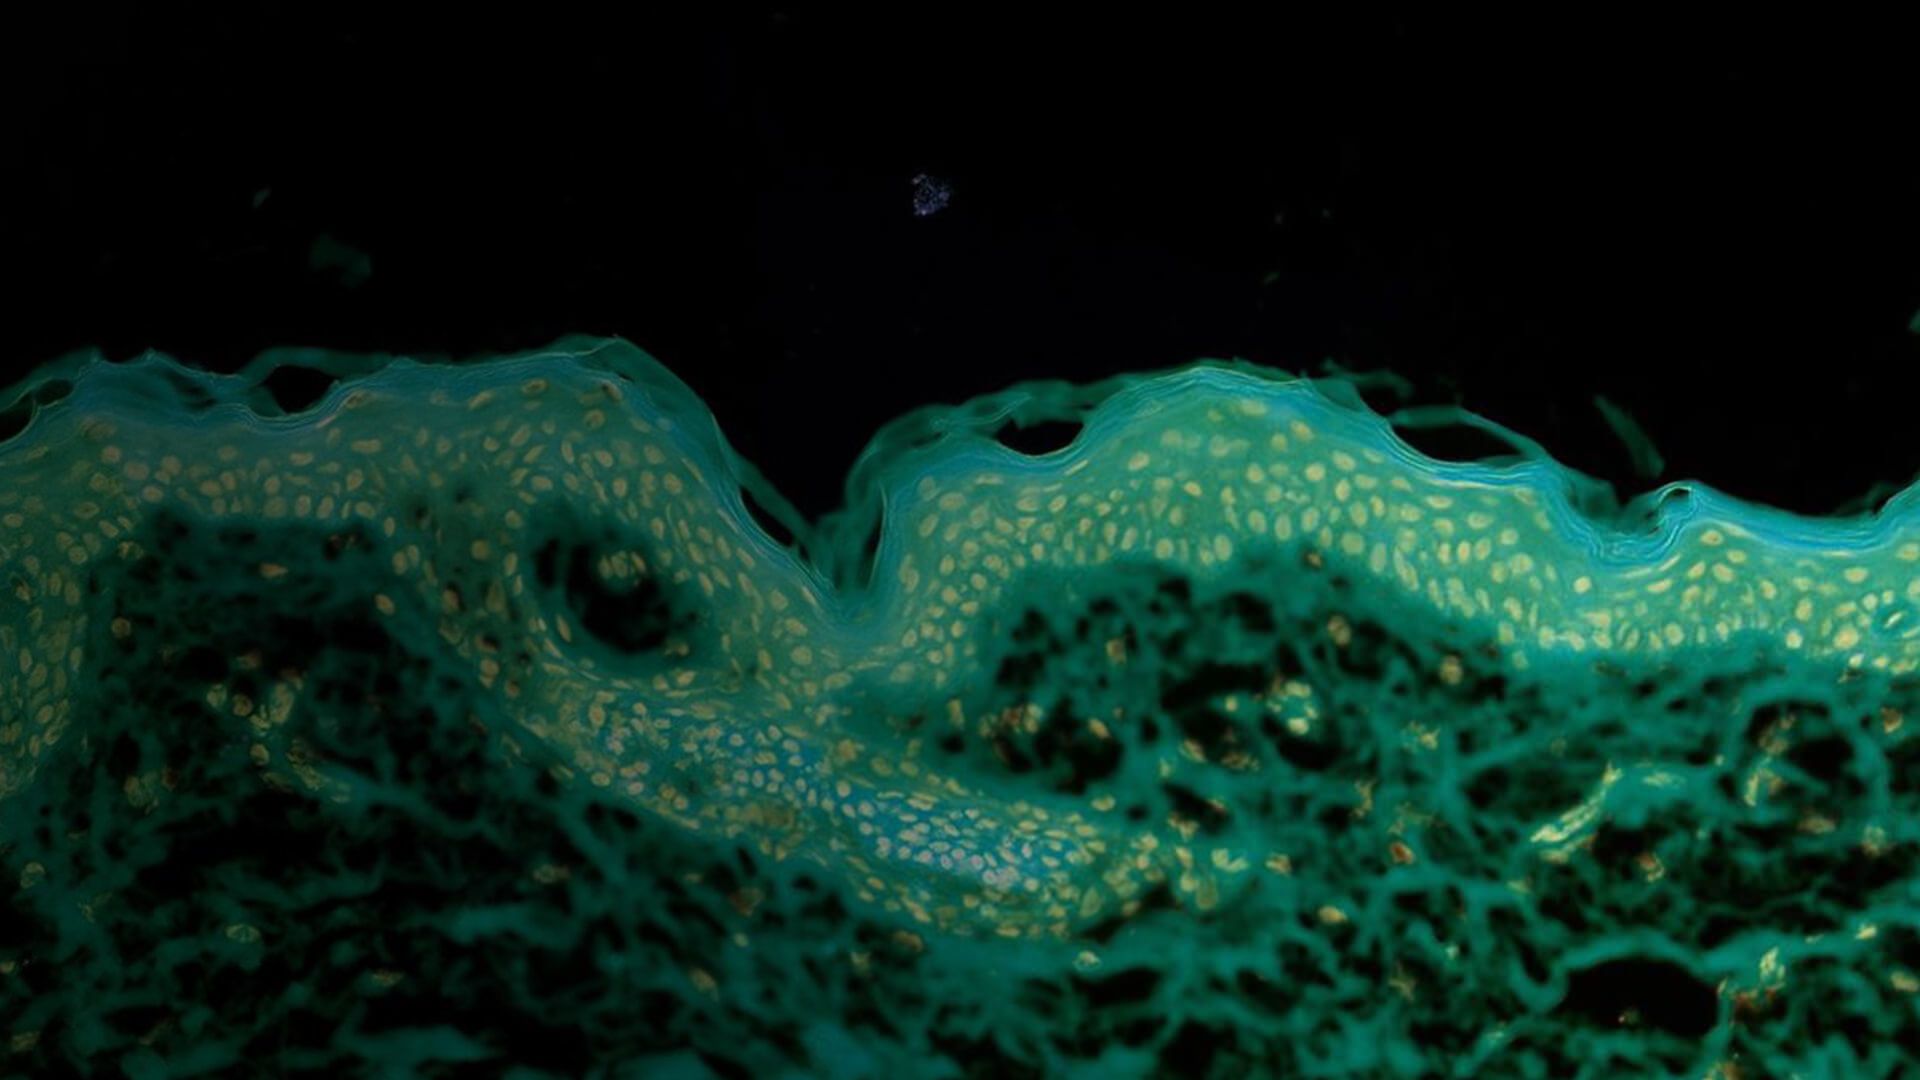

Stained human tissue section

Stained human tissue section